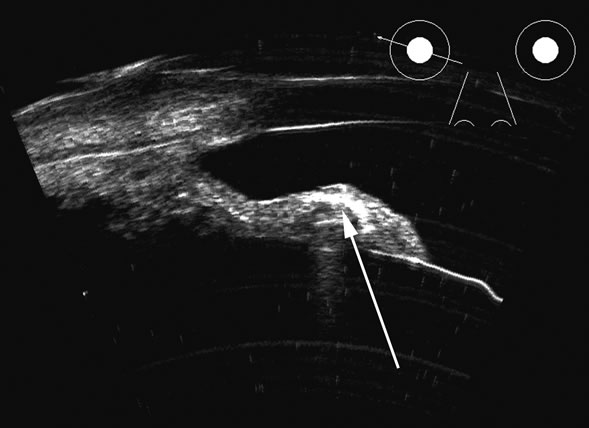

Fig. 12. Scleritis of the posterior pole produces an accentuation of the Tenon's surface posterior to the sclera and is commonly traceable to the meninges as they pass posteriorly along the optic nerve. This accentuated reflective “space” is often called a T-sign (arrow).